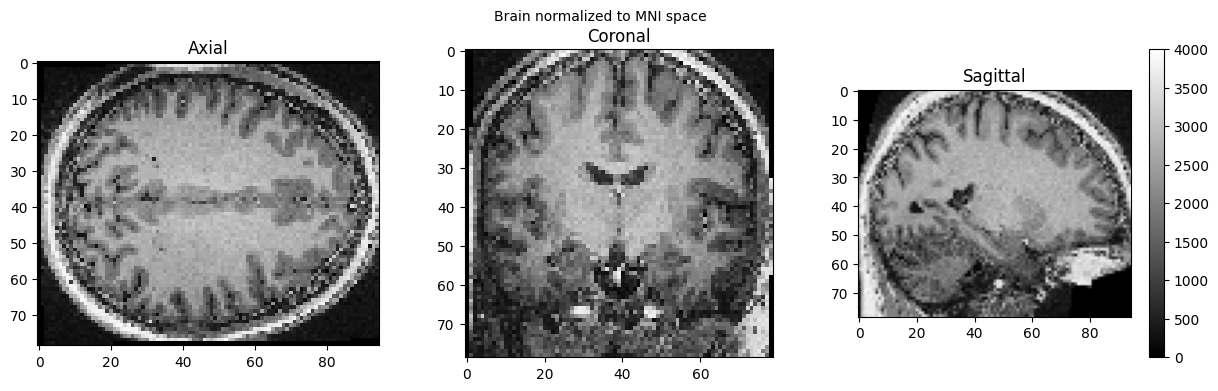

brain_full = nib.load('./wsub-01_ses-01_7T_T1w_defaced.nii').get_fdata()

view_slices_3d(brain_full, slice_nbr=50, vmin=0, vmax=4000, title='Brain normalized to MNI space')